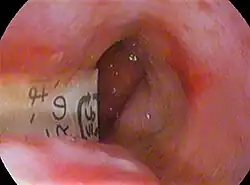

Foreign objects

Foreign body in esophagus